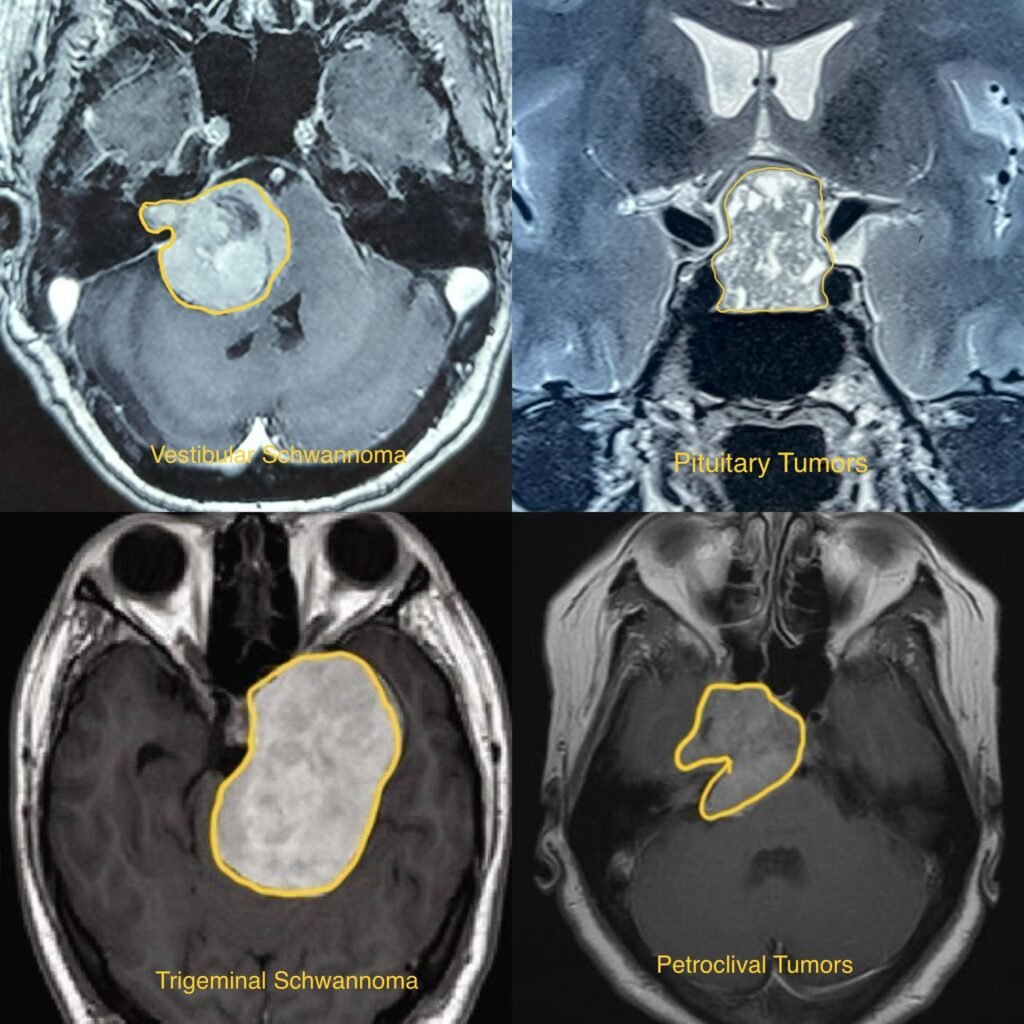

Skullbase Tumors

Skull Base Tumors are abnormal growths of cells that develop along the base of the skull, where the brain meets the facial structures. These tumors can originate from various types of tissues, including bone, cartilage, nerves, and blood vessels, and they can be benign (non-cancerous) or malignant (cancerous). Skull base tumors can be challenging to treat due to their location near critical structures of the head and neck.

• Diagnosis typically involves a thorough physical examination, medical history, imaging studies such as MRI or CT scans, and sometimes biopsy to determine the type and grade of the tumor.